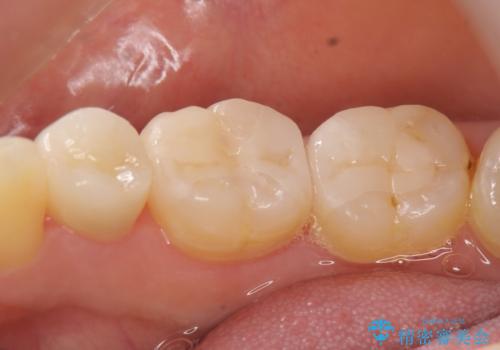

セラミックインレーによる虫歯治療

- 矯正治療希望で来院され、左上5に大きな虫歯があった患者様の症例です。虫歯除去後、矯正中はプラスチックによる仮詰めを行い、矯正終了後プラスチックを除去し、セラミックインレーで再補綴しました。

セラミックインレーによる修復

当院のセラミックインレーはemaxという強度と審美性に優れた材料を使用しています。

またプレス方式でインレーを製作しているため、削り出しで製作するCADCAMより優れた適合性も持ち合わせており、二次的な虫歯になりにくい修復物です。